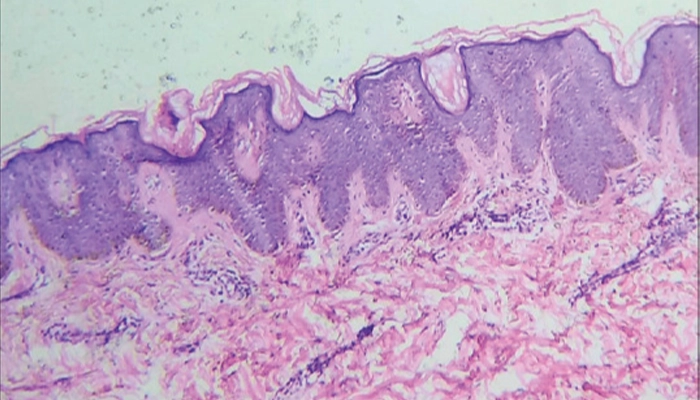

4.3. Sinh thiết da

Thường không cần thiết để chẩn đoán bệnh gai đen điển hình. Sinh thiết được chỉ định khi tổn thương không điển hình hoặc cần loại trừ bệnh lý da khác.

Hình ảnh sinh thiết da trong bệnh gai đen